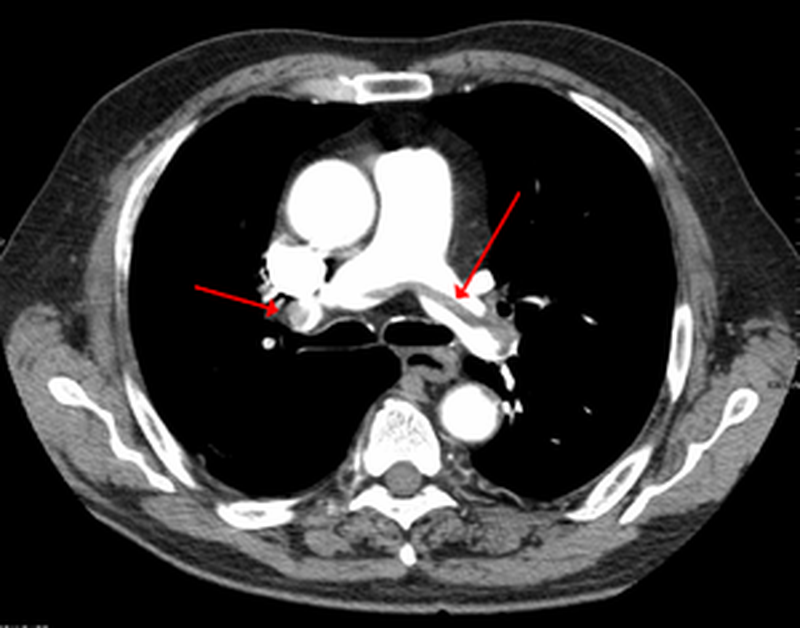

Pulmonary embolism is a blockage in one of the pulmonary arteries in your lungs. In most cases, pulmonary embolism is caused by blood clots that travel to the lungs from the legs or, rarely, other parts of the body (deep vein thrombosis). Because the clots block blood flow to the lungs, pulmonary embolism can be life-threatening. However, prompt treatment greatly reduces the risk of death. Taking measures to prevent blood clots in your legs will help protect you against pulmonary embolism.